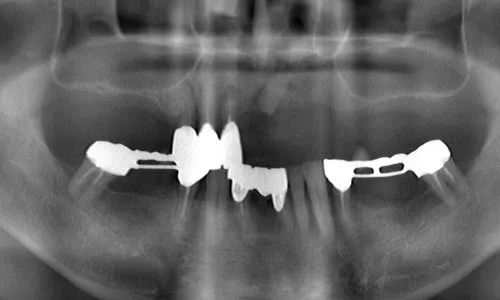

症例②

| 主訴 | 食事ができない |

| 診断名 | 咀嚼障害 |

| 年齢 | 58歳 |

治療に用いた装置(治療法) | 上顎:オールオン6 |

| 部位 | 上顎:右上7・右上5・右上2・左上4・左上5・左上6 下顎:右下7・右下6・左下5・左下6・左下7 |

| 治療期間 | 1年 |

| 治療費用 | 上顎:3,800,000円 下顎:2,310,000円 |

| リスク・副作用(治療に関する) | 腫脹しびれ |